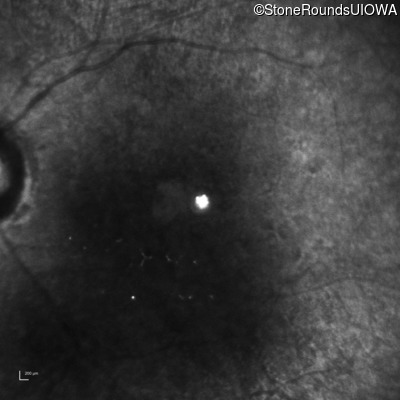

The clinical features supporting the diagnosis of Bardet Biedl syndrome in this patient include: bone-spicule-like pigmentation, narrowed arterioles and macular atrophy on ophthalmoscopy; photoreceptor loss on OCT; ulnar polydactyly, obesity, abnormal cognition, hypertension; and, normally sighted parents.